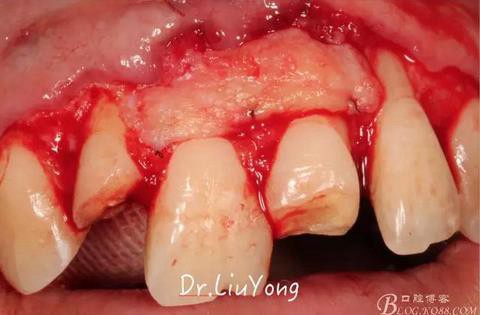

系帶手術(shù)后兩周,進(jìn)行上頜前牙唇側(cè)的牙齦退縮的手術(shù)治療,由于局部附著齦缺如及牙齦厚度不足,因此同期進(jìn)行上皮下結(jié)締組織移植,解決附著齦及牙齦厚度不足的問(wèn)題。

術(shù)中,可見(jiàn)明顯的唇側(cè)骨開(kāi)裂,如上圖

A區(qū)腭側(cè)所移取的上皮下結(jié)締組織瓣,如上圖